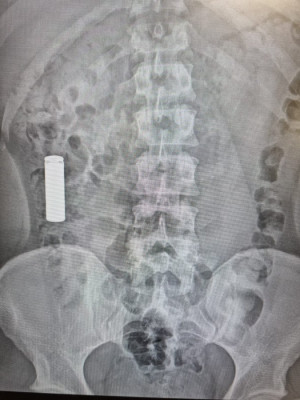

No es fácil pillar a ilegales por las calles. Nadie va diciendo quién es ilegal o quién no. En los hospitales cuentan un caso común. Llega una persona que se ha tragado una pila... y ve su plazo de estancia en España ampliado 90 días... con lo que la deportación se aplaza; y cuando pase el plazo podrá esperar otra circunstancia desgraciada en la que le pillen como ilegal... y comienza el proceso de tragarse otra pila. Dicen que son las ONG las que asesoran así:

Me parece un poco exagerado, que se traguen una pila para ir a urgencias y allí les ingresen y les autorizan una estancia prolongada en dos meses.